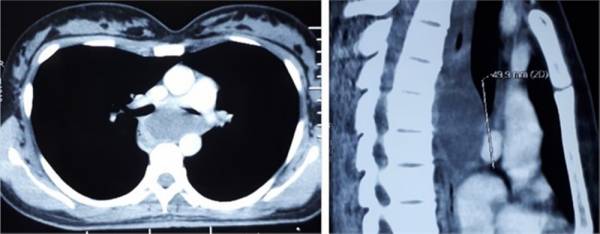

Phim chụp CT của bệnh nhân. (Ảnh: Bệnh viện cung cấp)

Ngoài ra, trong quá trình nội soi ống tiêu hóa, nội soi phế quản cũng phát hiện hình ảnh từ ngoài đè vào thực quản, hẹp nhẹ lòng phế quản đoạn sát carina do đè ép từ ngoài. CT scan ngực có hình ảnh khối bệnh lý trung thất, bờ đều rõ, kích thước 29 x 53mm, đậm độ 22HU, ngấm thuốc kém.

Tổn thương đề đẩy lệch thực quản ra sau và sang phải, đẩy khí quản và phế quản gốc hai bên ra trước và gây hẹp phế quản gốc; không thấy rõ ranh giới với thành thực quản.